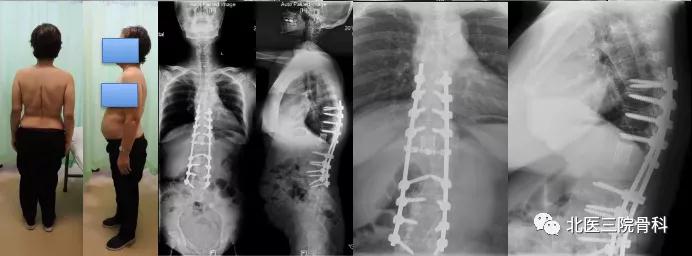

病例六

腰椎退变性侧弯大体照及影像学

(术前)

(术后)